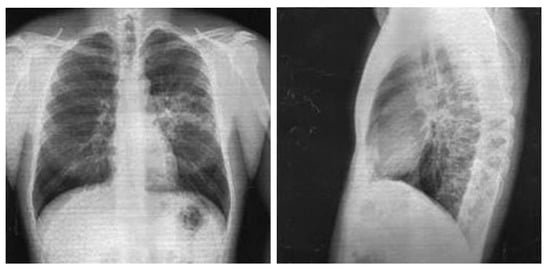

Chest X-ray in anteroposterior and lateral views, dated 27 November 2017, revealed a low-intensity infiltration in the S6 projection of the left lung. The roots were structural. The pleural recesses were clear. The cardiac shadow was unchanged (Figure 2).

Figure 2. Chest X-ray of Patient P. (28 November 2017).

On 7 December 2017, the follow-up complete blood count showed: WBC, 8.4 × 109/L; RBC, 5.1 × 1012/L; hemoglobin, 153 g/L; neutrophils, 2%; segmented neutrophils, 51%; monocytes, 10%; eosinophils, 1%; lymphocytes, 36%; platelets 380 × 109/L, ESR, 10 mm/h. Urinalysis, blood chemistry, and ECG revealed no abnormalities. Chest X-ray in anteroposterior and lateral views performed on the same day showed the resolution of infiltration with slightly increased local vascularity and consolidation.